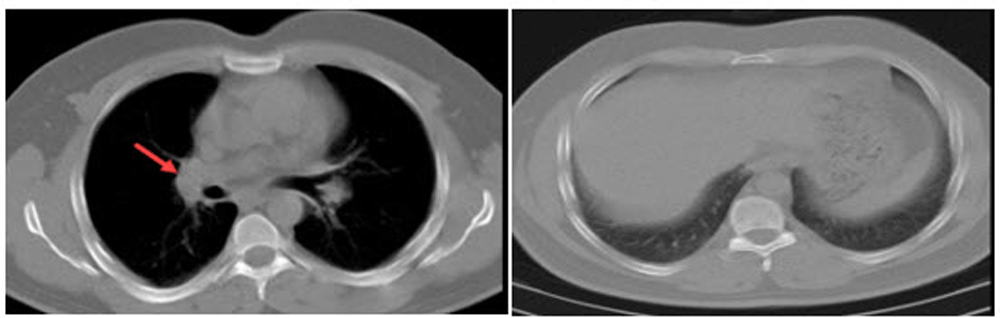

A 39-year-old man, taxi driver, known to have hypothyroidism (being treated with levothyroxine) presented to the emergency ward with dyspnea and coughing after exposure to detergents in a closed environment. The patient was smoker (3 pack/year). The only in clinical examinations except for wheezing in the right side of chest. The patient's chest radiography identified a mass. For further investigation, a spiral computerized tomography (CT) scan was performed. Lymph nodes were enlarged on the right side of the trachea, measuring about 23 mm with a mass of 70 × 77 mm, in the vicinity of the right lung hilum. A hypodense nodule in the posterior part of the liver, suspected to be malignant, was also reported (Figure 1). The lesions were suspected to be metastatic tumors, therefore, a biopsy of the mass was performed via bronchoscopy. The biopsy results were reported as chronic inflammation and mucosal hyperplasia without malignancy, which did not conform to the CT report. The CT has repeated again, and confirmed the previous CT report. A CT guided mass biopsy was performed for pathological evaluation. The result showed chronic granulomatous inflammation, the two most likely causes being tuberculosis (TB) and sarcoidosis. Sputum smear, culture, and PCR were performed to test for TB, and angiotensin-converting enzyme (ACE) levels were measured for sarcoidosis. The results ruled out TB and showed high levels of ACE (ACE = 88 (normal 8-53)). Two months after the first visit, sarcoidosis was diagnosed and treatment started with prednisolone. Ophthalmology test for eye evaluation, echocardiography for cardiac evaluation and EMG/NCV (Electromyogram test and nerve conduction study) for evaluation of the nervous system were also performed to determine if there was any extra-pulmonary sarcoidosis, however, no lesions were found. After treatment by corticosteroid the symptoms of the patient subsided. Now the patient is on follow-up. Figure 2 show the CT scan of patient after treatment.